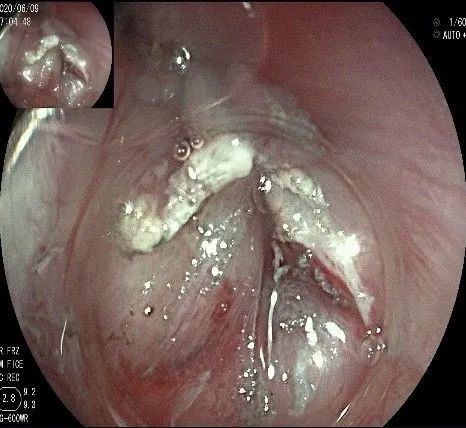

沿切开的边缘,从口侧开始向下进行粘膜下剥离,剥离的间隙是瘤体之上粘膜之下,期间反复进行粘膜下注射。

随着剥离的进行,瘤体与周围组织的关系越来越清晰。

此时瘤体基底部已暴露出来,起源于固有肌层。

这是最后的“根”部。

换用IT刀可以轻松剥离,又避免切入过深造成穿孔。